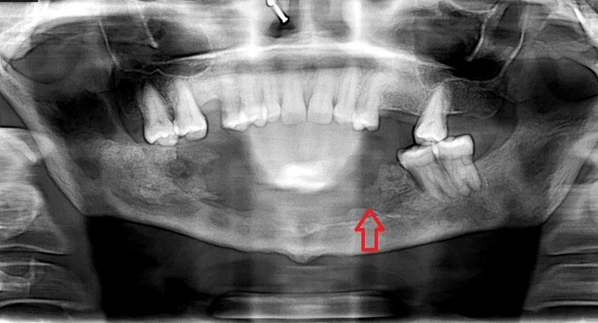

Case 3: A 51 year old lady presented with left sided jaw pain for 1 month. She is a known patient of hypertension and diabetic nephropathy. She was admitted with moderate Covid- 19 pneumonia and received dexamethasone 6mg twice a day followed by 6mg once a day for total 21 days, remdesivir and supplemental oxygen 6 months before presentation. There was no prior dental procedure or tooth extraction before her symptoms started. All para nasal sinuses were normal clinically. Sinus endoscopy was normal. HbA1C was 10.3%.

Z-orthopantomogram showed left mandibular erosions with affected tooth had spontaneously fallen off (Figure 4). She underwent complete debridement and histopathology from the intra operative specimen showed broad aseptate fungal hyphae with obtuse angle branching alongwith bony and angioinvasion. Fungal culture was not sent from dental surgery where she was initially admitted. Due to multiple comorbidities she was not offered injection amphotericin b due to its known toxicities and treated with tablet posaconazole for 3 months. Her trough posaconazole concentration was found to be 1570 ng/ml and she did well with this therapy.